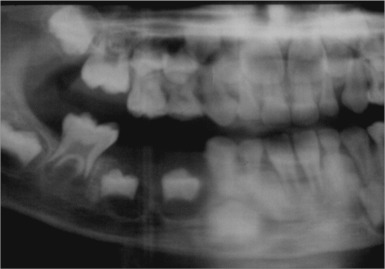

76.顎骨中柏奇特氏淋巴瘤(Burkitt’s lymphoma)之放射線影像,最常呈現為下列何者?

(B)界線不清楚之放射線透過性病變(radiolucent lesion)